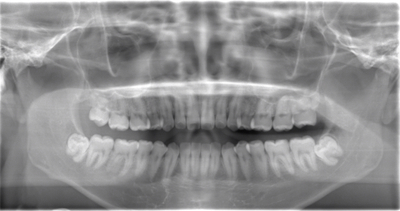

CASE 2

| 年齢・性別 | 30代・男性 |

| 主訴 | 左上下親知らず抜きたい |

| 抜歯期間 | 30分 |

| 抜歯費用 | 約2,500円(保険内) 別途CT撮影で3,000円 |

| 抜歯内容 | 左上下の親知らず抜歯 |